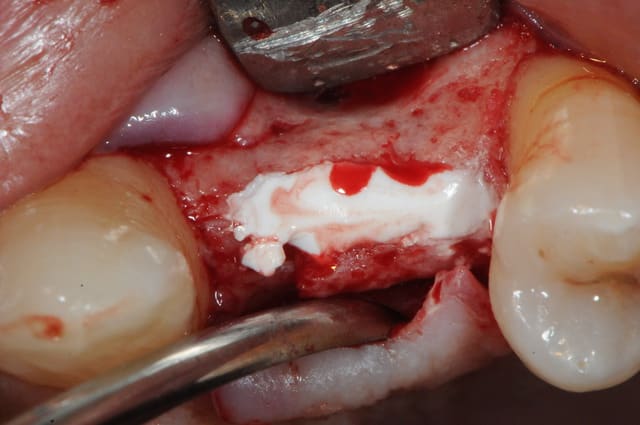

je me permet d'apporter un maigre contribution à ce poste.

mais avant, tout un petit historique du cas...

il y a 15 jours donc.

1 : 24 abscente et 25 distalé

2: mise en évidence de l'espace trop important

Plan de traitement: pose implant 24 puis utilisation de cet implant comme ancrage absolu pour mésialer 25.

3 : vu de dessus/dessous

4 : incision crestale - lambeau de pleine épaisseur

5 : incision de la corticale osseuse avec disque diamanté Komet

6 : bone spliting (pas top, je l'avoue) avec ciseaux à os (aesculap je crois)

(je donne la marque , mais je touche rien!!! c'est juste pour info)

7 : système D pour ceux qui pas équipé de Tatum, un simple décolleur de Molt

8 : pose implant

9 + 10: vital os et sutures.

tu parles! nécrose osseuse, exposition de l'implant et de la crête osseuse photo 1 et 2

donc pince gouge pour l'os "mort" cruantage de berges gingivales, irrigation, sutures bref, je fais le pompier de service.

photo 3: contrôle à 4 jours, le plus grave est passé!

n’empêche que les dégâts sont considérables...la tête de l'implant est exposée.